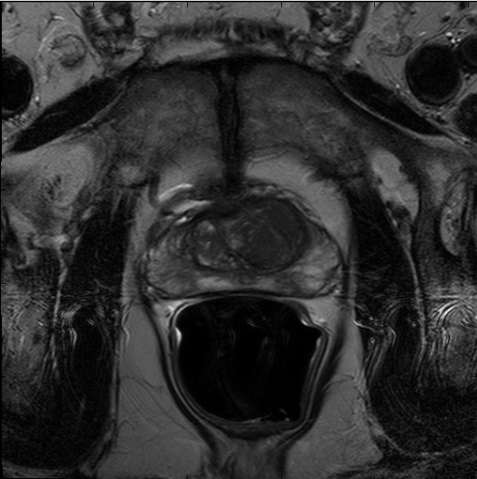

We trained our network on 77 patients. The input images and the manual ground truth annotation are shown in Fig.4. As we have described above, these images were acquired from different patients, and these images include the clinical variability. To evaluate our method, we randomly selected 4 patients with 64 images before training. These images do not take part in training and the prostate has been manually pre-delineated by a radiologist, which were used as the ground truth to evaluate the performance of automatic segmentation. We also selected dice coefficient as the evaluation method[30]. And to validate our method against U-Net and fully convolutional networks (FCNs), we used the same dataset to train and test the U-Net and FCNs.

To intuitively compare the proposed method with U-Net and FCN, the segmentation results of some representative and challenging samples are shown in Fig 5. It can be seen that these prostate images have fuzzy boundaries and the pixel intensity distributions are inhomogeneous both inside and outside of the prostate. Besides, both prostate and nonprostate regions have similar contrast and intensity distributions. All of these phenomenons make the segmentation difficult.